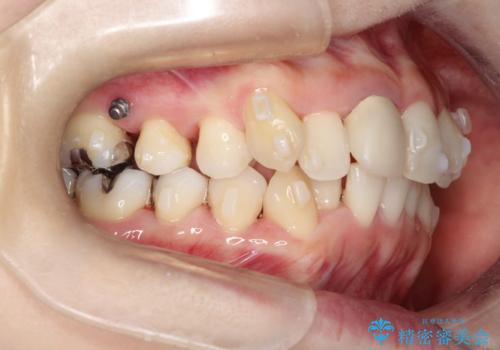

上下のガタガタのマウスピースによる非抜歯矯正

- 上下のがたつきを主訴に来院された患者様です。

上下の前歯と奥歯にがたつきがありました。

上下の奥歯を後方に移動させるのと、歯と歯の間をわずかに削ることでスペースを作り、歯を並べる計画としました。

インビザラインにて治療を行いました。

比較的がたがたの度合いが大きかったですが、しっかりとマウスピースを使用していただけたので、順調に治療を終えることができました。